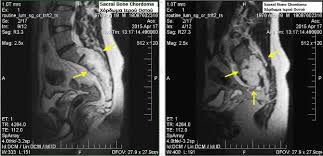

About 50% of chordomas occur in the sacrum, the bone at the base of the spine that forms part of the pelvis. The overall survival rates are 68% at 5 years and 40% at 10 years. These numbers are for some of the more common types of brain and spinal cord tumors. Chordoma is a bone cancer that belongs to the sarcoma family. Chordoma tumor cells arise from cells of the notochord the tissue in a fetus that acts as the building blocks for the spine.

They can affect adjacent organs, tissues, and bone. Chordoma patients have a long life expectancy with high mortality from the disease. Treatments for chordoma include surgery, chemotherapy, and radiation therapy. Because there are so few people with chordoma, these rates may not be very accurate. 31+ chordoma cancer life expectancy pictures. Chordoma tumor cells arise from cells of the notochord the tissue in a fetus that acts as the building blocks for the spine. Chordomas are rare, malignant tumors arising in the spine but which can spread elsewhere. About 50% of chordomas occur in the sacrum, the bone at the base of the spine that forms part of the pelvis. These include the nerves that control. Life expectancy patients with spinal cancer have a median survival term of up to several months from the diagnosis. Chordomas are rare, malignant tumors arising in the spine but which can spread elsewhere. When it occurs at the base of the skull, it is known as skull base chordoma. But sometimes a few of these cells remain and, rarely, they can become cancerous.